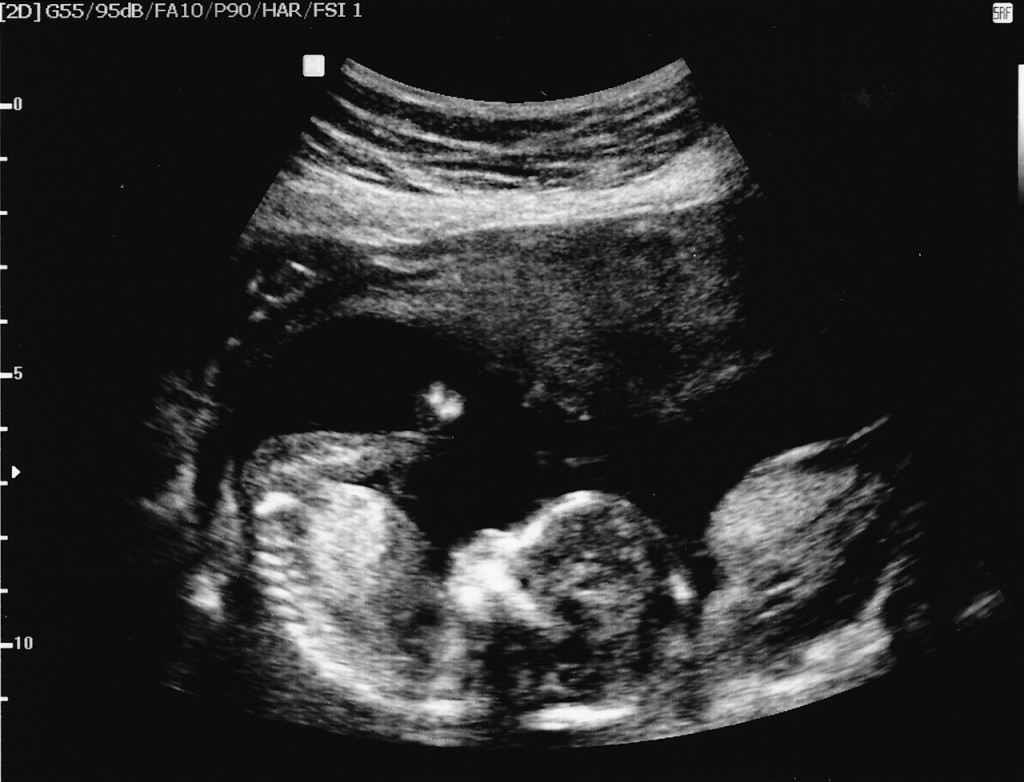

Categories events It’s a Girl! 16 Week Ultrasounds Post author By sean Post date September 7, 2012 Second set of ultrasounds, to help narrow the due date. At an estimated 16 weeks, we now know we are going to have a girl! Tags girl, ultrasounds